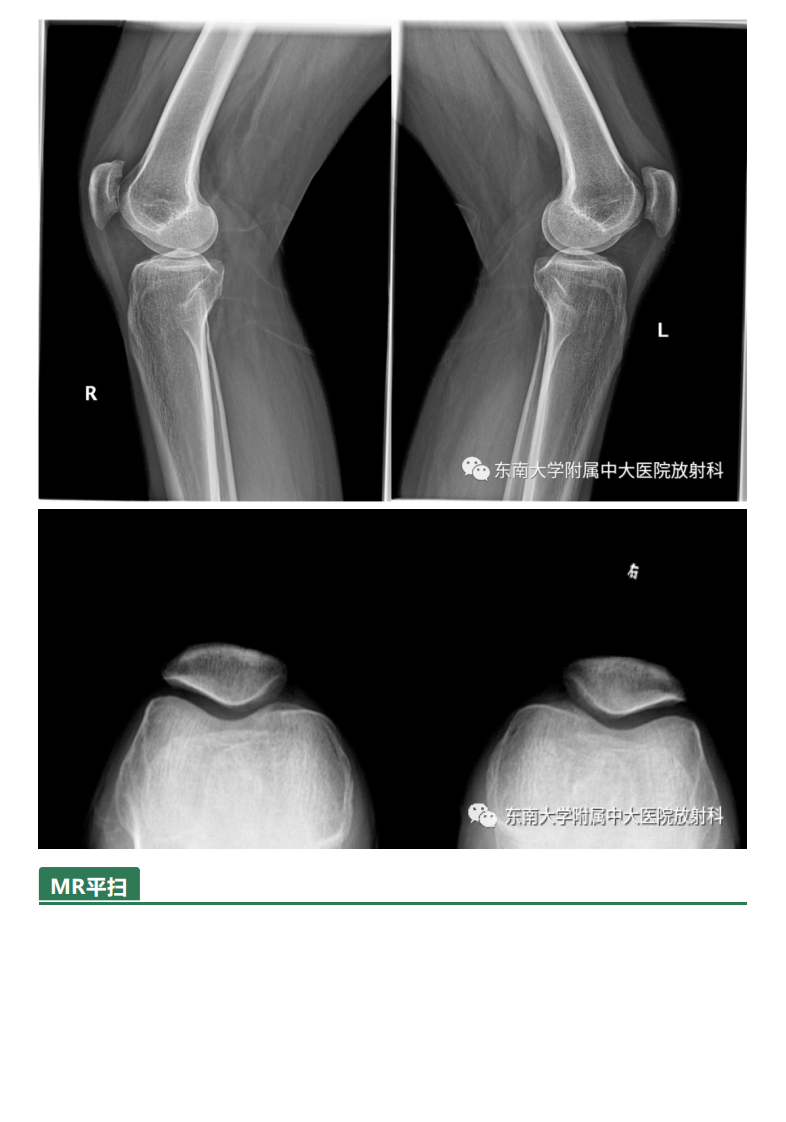

20210506_3【晨读结果公布】2021.05.06肌骨系统疾病——髌骨软化症.pdf